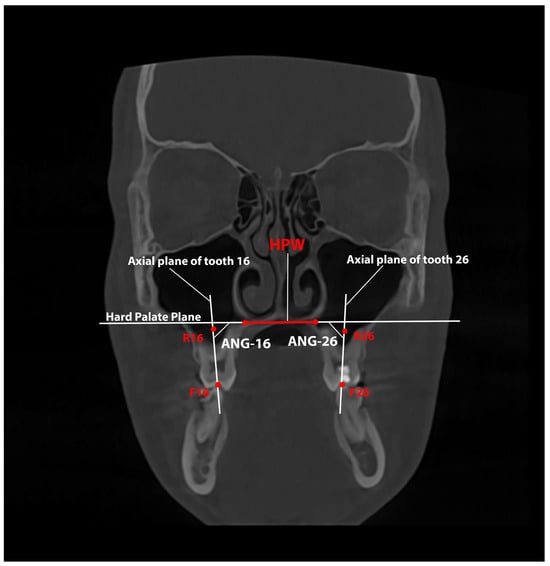

Changes and Correlations Between the Width and Height of the Hard Palate During Rapid Maxillary Expansion with a Printed Tooth-Borne Expander

Background/Objectives: The nasomaxillary complex is a compound anatomical structure in which the correlation between changes in palatal width and height has been poorly investigated. Methods: A three-year prospective study with 28 patients treated with printed expanders was conducted. Measurements on CBCT images were performed before and after treatment; the width and height parameters were measured on a coronal slice of a CBCT image at the level of the first molars and upper first molar inclination relative to the palatal plane. Results: A significant difference was found between the values measured before and after treatment, including an increase in the measured width parameters and a statistically significant decrease in palatal height (0.75 ± 0.97). The mean change in the upper molar inclination was not significant (tooth 16: 0.60 ± 6.42; tooth 26: 2.19 ± 4.51). The regression analysis did not establish a significant correlation between the expansion of the maxillary occlusal width and palatal height change or a significant correlation between the increase in the upper molar inclination and palatal height change. Conclusions: The use of a printed tooth-borne expander causes predictable and reproducible skeletal changes. It is a feasible treatment option, allowing for precise screw positioning to achieve bodily movement of the teeth and decrease the change in molar inclination. Full article